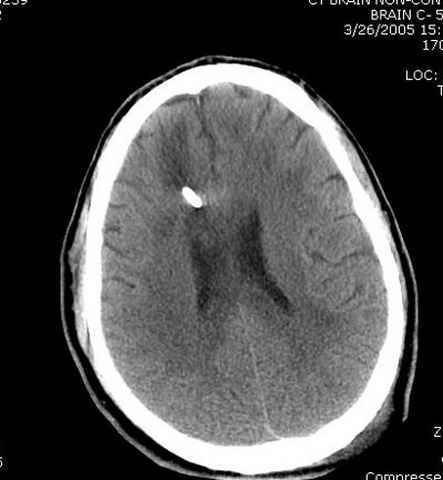

Наблюдается службой травмы и нейрохирургии (ICP) Increased Intracranial Pressure by ventricular cateter

больной без сознания, со слов нейрохирурга, наблюдается положительная динамика в нейрохирургическом статусе.

монииторинг

-Согласен, рана до прихода пластического хирурга была 38х13 см, можно было постараться закрыть сверху, а в нижнем отделе где был ожог, применить кожную пластику меньшим размером. К моему удивлению и разочарованию, когда вернулся из другой операционной (шли пареллельные операции), он уже успешно заканчивал свое дело. Кстати недавно разговаривал с нейрохирургом, он снял ICP (intracranial prеssure monitor), внутричерепное давление стабилизировалось, ортопеды и хирурги закончили с лечением, теперь длительное неврологическое восстановление.